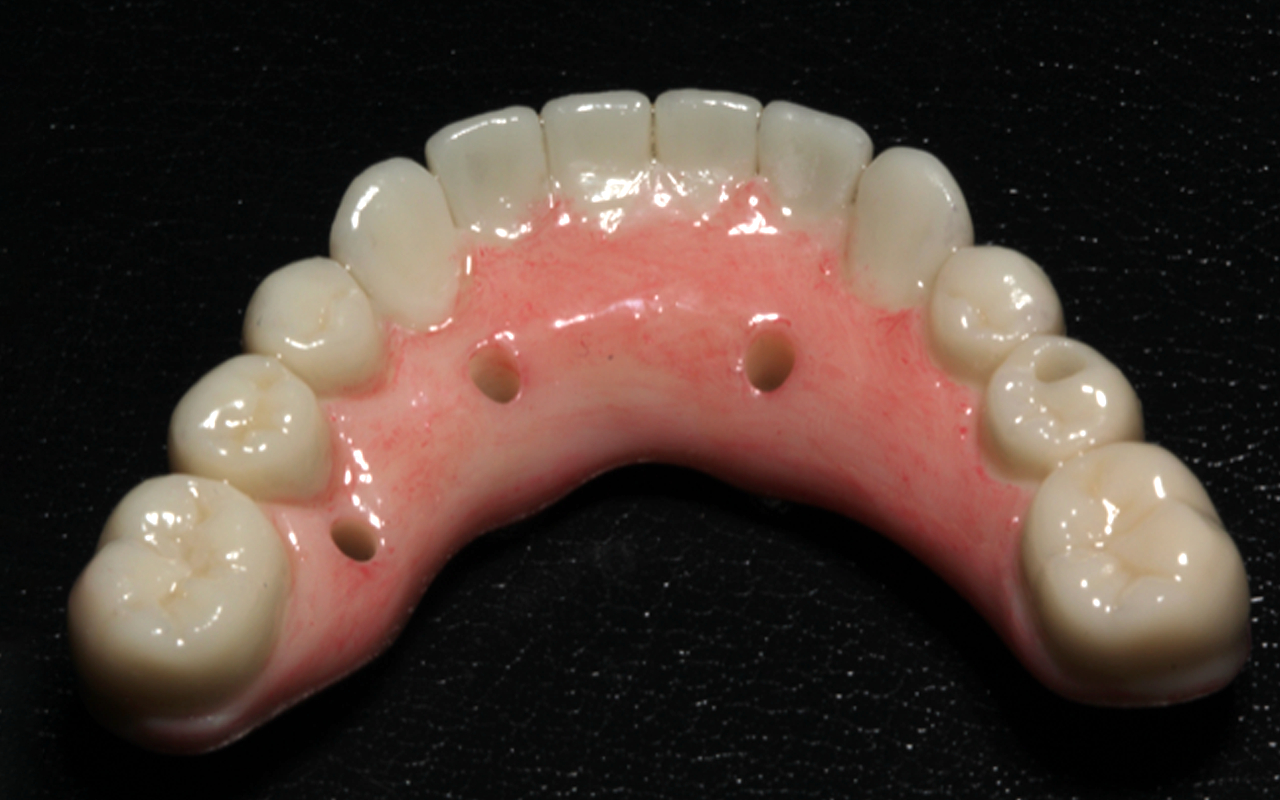

Full arch patient surgery with 3D surgical and stackable guides, implant scanning protocols with 3Shape and photogrammetry with PIC scanner and delivery of 3D printed full-arch provisionals.